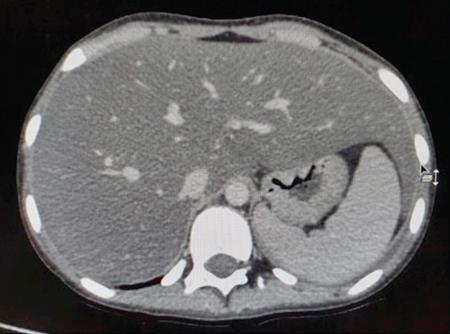

DIFFUSE PARENCHYMAL DISEASES OF THE LIVER Ishan Kumar, Ashish Verma The hepatic parenchyma is the site for multiple essential, interrelated, and complex metabolic activities to assimilate nutrients, detoxify the body, and synthesize vital molecules such as enzymes, hormones, cofactors and essential components of the coagulation pathway. The chemical reactions involved in each of these activities pose a threat to the hepatocytes, which may be damaged leading to the initiation of reparative processes. Further, the liver, being a highly vascular organ with multiple metabolic activities, is liable to be involved in many systemic vascular and metabolic disorders. On one hand, such changes cause healing of the tissue injury, but on the other hand, lead to diffuse parenchymal changes, which may result in suboptimal functioning of the organ. Such a condition is labelled as ‘diffuse liver disease’ and includes (a) diseases caused due to storage of certain chemical products of such chemical reactions labelled as ‘storage disorders’, (b) diseases caused due to reduction of blood flow to the organ, (c) parenchymal injury due to stasis of bile at various levels in the pathway due to varied causes, and (d) involvement of liver in systemic or organ-based inflammatory disorders. The mainstay of diagnosis of diffuse liver diseases is the detection of alterations in the biochemical parameters in blood indicative of liver function, which however is nonspecific to various aetiologies. The diffuse liver diseases in children are quite different from those in the adult population and constitute mainly of congenital or inherited metabolic and vascular diseases as opposed to diseases of acquired aetiologies in the latter population. The gross and microscopic pathological changes are accordingly different in the paediatric population and may be utilized to add specificity to the biochemical indicators as far as aetiological diagnosis is concerned. The invasive and potentially hazardous sampling mandated for histological evaluation of liver parenchyma has been replaced by an array of imaging modalities in recent times. The present chapter presents a review of the currently available imaging modalities (viz. cross-sectional imaging modalities such as ultrasonography, computed tomography [CT] and magnetic resonance [MR] imaging) for evaluation of diffuse liver diseases along with the pertinent imaging features and guidelines for their rational use in various indications. Also a short review of certain key technical and technological details is included. Jaundice and hepatomegaly are the most common clinical manifestations of liver disease. Anorexia is a nonspecific sign, often present in acute or chronic liver disease. Jaundice is a sign of increased bilirubin content in the blood, that can exist in four forms: (i) unconjugated bilirubin bound to albumin, (ii) unbound unconjugated bilirubin, (iii) conjugated bilirubin and (iv) δ fraction. Direct fraction includes both conjugated bilirubin and δ bilirubin. Conjugated hyperbilirubinemia is due to decreased excretion by liver or biliary tract obstruction. Pruritus, spider angioma on face and neck, ascites, portal hypertension, botchy palmer erythema, subcutaneous xanthoma, gastrointestinal (GI) variceal bleed, encephalopathy, renal dysfunction and pulmonary involvement are manifestations of advanced cirrhosis. Evaluation of total serum bilirubin and its fractional analysis into indirect (unconjugated) and direct (conjugated and δ fraction) bilirubin helps to distinguish between elevation caused by haemolysis and that due to hepatic dysfunction or biliary obstruction. Elevations in alkaline phosphatase (ALP), 5′ nucleotidase, and γ-glutamyl transpeptidase (GGT) levels are an indicator of biliary obstruction. However, it should be noted that normal growing children have significant elevations of serum ALP activity. AST (aspartate aminotransferase) and ALT (alanine aminotransferase) are significantly raised in acute hepatitis. ALT rise disproportionate to AST rise is seen in viral hepatitis. A predominant rise in AST is seen in echovirus infection, various metabolic diseases or alcohol-induced hepatitis. These aminotransferases are also elevated in NAFLD/NASH. ALT/AST rise is less marked in chronic liver disease. PT-INR, serum albumin levels can evaluate the hepatic synthesis function. Hypoalbuminemia suggests a bad prognosis. γ-Globulin is elevated in autoimmune hepatitis (AIH). Alpha-fetoprotein is raised in hereditary tyrosinemia or hepatic neoplasms. Indications of liver biopsy in the paediatric age group include neonatal cholestasis, metabolic liver disease, NAFLD, congenital hepatic fibrosis, abnormal biochemical liver tests of unknown aetiology, intestinal failure associated liver disease, acute liver failure and liver tumours. Although biopsy of children and infants is considered a safe procedure, due to incidences of shock, the North American Society for Pediatric Gastroenterology and Nutrition (NASPGHAN) has recommended liver biopsy in children not to be necessarily performed as outpatient procedures. Sonography-guided percutaneous liver biopsy has been reported to be safer, more efficient, more comfortable and only marginally more expensive than blind biopsy. The use of coaxial technique, determination of the number of passes and use of track embolization were at the discretion of the interventional radiologists. In cases of uncorrected PT-INR elevation, transjugular liver biopsy can be performed. Ultrasound (US) is a valuable tool in the diagnosis and management of diffuse liver diseases. It provides useful information about the size, surface, parenchymal architecture, biliary channels and blood flow of the liver. US examination of the liver is performed in the supine position with a convex (5–7.5 MHz) probe. High-frequency (7.5–12 MHz) linear transducers can be used in young infants because of their small size. US examination can be completed with the colour Doppler technique and US elastography, if needed. CT protocol typically requires image acquisition during the multiple phases with a slice thickness of 5 mm or less and a pitch ranging from 1 to 1.5. Contrast injected is 2 mL/kg through manual or mechanical injection. The arterial phase begins at 10–15 seconds and the portal phase is at 20–40 seconds after contrast injection. Equilibrium phase is obtained at 3 minutes, when needed. MRI protocol to evaluate paediatric liver chiefly includes free-breathing sequences, due to the challenge offered by an inadequate breath-hold in these patients. Due to the same reason, motion insensitive single-shot HASTE sequences or motion insensitive T1-weighted spoiled GRE single-shot sequences are also widely utilized in paediatric MR examinations. In slightly older children with a relatively uniform breathing pattern, external trigger signals from a breathing belt, or navigator techniques may be used to overcome motion artefacts from breathing. T1- and T2-weighted turbo spin-echo (TSE) sequences and T2-weighted single-shot sequences in axial and coronal planes are initially acquired to evaluate the anatomy and screen for pathologies. This is followed by a gradient echo (GRE) images to examine vascular structures. Multiecho images with T1-weighting can be acquired to evaluate the fat content of lesions. Contrast-enhanced MRI with intravenous injection of gadolinium (Gd)-based contrast agent is performed as routine in cases with suspected portal hypertension or in any associated suspected neoplastic lesion. This is usually clubbed with MRA for vascular mapping. Arterial phase and portal phase should be acquired 10–15 seconds and 20–30 seconds, respectively after the start of contrast agent injection. GRE T1-weighted sequence should be repeated continuously four or five times to include achieve all phases of liver perfusion. Finally, steady-state imaging should be performed in the equilibrium phase (3 minutes) using T1-weighted and T1-weighted fat-suppressed imaging sequences. MRI contrast media should be administered with caution after evaluation of eGFR, and is safer than the iodinated contrast media needed for CT scan examination, and is hence preferred. Liver size measurement is commonly obtained in one of the two ways (a) an anterior to the posterior measurement of the liver in the midclavicular line, (b) a dome-to-tip longitudinal measurement of the liver in the midclavicular line. Table 9.8.1.1 provides suggested upper limit values of liver and spleen length for various paediatric age groups. Despite advances in 3D US, volume measurements of liver size have not been incorporated in the routine clinical practice because it is time-consuming, requires considerable skill and technically difficult fusion of multiple 3D sweeps. Nonalcoholic fatty liver disease (NAFLD) is referred to as triglyceride accumulation in hepatocytes and encompasses a broad range of clinicopathological entities ranging from simple steatosis, steatohepatitis to cirrhosis. Its worldwide reported prevalence is approximately 2.6%–10% in the general paediatric population and as high as 38% of obese children under the age of 19 years. In India, the reported prevalence is as high as up to 22% in the general paediatric population and up to 45% in obese and overweight children. Hepatic steatosis currently is the most common cause of chronic liver disease in paediatric patients. Table 9.8.1.2 highlights the causes of hepatic steatosis in paediatric age group. The pattern of injury is similar to alcoholic liver disease. Nonalcoholic steatohepatitis (NASH) constitutes a subset of NAFLD, ranging from simple steatosis to inflammation and fibrosis. NASH in children has two distinct histological subtypes. Type 1 NASH resembles adult subtype with macrovesicular steatosis, lobular inflammation, and ballooning degeneration and perisinusoidal fibrosis. Type 2 NASH shows steatosis with portal fibrosis and is present in younger children with increased severity of obesity. ALT can be normal in 20% of the patient with NAFLD and liver biopsy is the gold standard for diagnosis as well as a semiquantitative assessment of disease severity. In clinical practice, the diagnosis and monitoring of NAFLD largely rely on ultrasonography. Grade I fatty liver refers to diffusely hyperechoic parenchyma with a well-visualized diaphragm (Fig 9.8.1). Bright liver with loss of periportal echogenicity and indistinctly visualized vessels is referred to as grade II and blurring of the diaphragm is classified as grade III fatty liver. Limitations of the US are lack of objective quantification and diminished sensitivity in cases where biopsy-proven steatosis ratio is less than 30%. Moreover, hepatic fibrosis and inflammation in cases of NASH are sonographically indistinguishable from simple steatosis. Contrast-enhanced US can diagnose the presence of fibrosis in NAFLD, which is evident from the decreased accumulation of microbubbles in the liver parenchyma. The distinction between hepatic steatosis and fibrosis is important clinically, as fibrosis can progress to cirrhosis if left untreated. US elastography has emerged as a promising technique to screen the children with NAFLD to look for ongoing steatohepatitis/fibrosis. Transient elastography is the most popular elastography technique which has shown excellent accuracy in the adult population with chronic hepatitis. However, its accuracy in NAFLD is significantly lower and the data of effectiveness in the paediatric population is limited. Acoustic radiation force impulse imaging (ARFI) has been shown to have a good correlation with AST/ALT ratios in obese children with NAFLD. An ARFI elastography value of >1.19 m/s predicts NASH-related hepatic changes in these patients while a value >1.75 m/s is suggestive of cirrhosis. Another study on shear-wave elastography has shown a high correlation in paediatric NAFLD patients with biopsy-proven hepatic fibrosis. A value of >5.1 kPa strongly predicts the presence of fibrosis whereas a value of >6.7 kPa is suggestive of stage ≥F2 fibrosis (Brunt scoring system). CT is a common modality utilized for assessment of hepatic pathologies, however is seldom used for assessment of NAFLD because of the risk of ionizing radiation. On noncontrast CT, liver attenuation <40 HU or hepatic attenuation 10 HU lesser than that of the spleen is considered as a sign of steatosis. Recent literature advocates the utilization of MRI in the evaluation of NAFLD. Fat imparts high signal intensity to the liver parenchyma on T1-weighted spin-echo MR images while it is mildly hyper- to hypointense on T2-weighted images. Conventional spin-echo imaging is relatively insensitive to mild-to-moderate fatty infiltration of the liver. The most commonly employed technique for detection of steatosis is chemical shift imaging (Dixon technique or dual-echo method) which utilizes two sets of gradient-echo images of the liver, that is in-phase and out-of-phase. On in-phase echo-time, water and fat signals add whereas, on out-of-phase echo-time, water and fat signals cancel each other. In nonfatty livers, the signal intensity of the liver parenchyma is unchanged between in- and opposed-phase images whereas a fatty liver shows a notable reduction of signal intensity on the opposed-phase images. Iron deposition in the liver can interfere with the assessment of steatosis. MR spectroscopy has been one of the most reliable techniques for the evaluation of hepatic steatosis (Fig 9.8.1.2). Protons in water molecules resonate at 4.7 ppm while that in triglyceride molecules resonate predominantly at 1.3 ppm. Other smaller lipid peaks can be obtained at 0.9, 2.0, 2.2 and 5.3 ppm. In a healthy nonfatty liver no triglyceride peak should be present. The presence of fat can allow measurement of area under water peak versus area under fat peaks to procure hepatic fat fraction. Proton density fat fraction (PDFF) measurement by MRI is another promising objective technique for quantification of steatosis in the paediatric patient. PDFF is the ratio of the density of mobile fat protons and the total density of protons including that from triglycerides and mobile water. Magnetic resonance elastography (MRE) is suggested as a noninvasive tool to evaluate liver stiffness that correlates with the degree of fibrosis. The technique is based on measuring the propagation of shear waves through liver parenchyma. A cut-off value for liver stiffness of 2.27 kPa has been suggested to predict Ludwig grade 2 or higher fibrosis. The technique depends on measuring the propagation of shear waves through the hepatic parenchymal fibrosis and differentiation of low-grade fibrosis from high-grade and also it may be feasible to distinguish steatosis from steatohepatitis. Success rate and accuracy of MRE is higher than US-based transient elastography. Cirrhosis is referred to as diffuse end-stage chronic liver disease characterized histologically by fibrosis and nodular regeneration, along with the disorganization of liver architecture. Although various underlying aetiology can lead to cirrhosis in children (Table 9.8.1.3), the most common causes in India are posthepatitic cirrhosis, Wilson’s disease (WD), AIH, biliary cirrhosis, biliary atresia and other metabolic diseases. In 5%–15% cases, the cause of cirrhosis may remain undetermined and is known as cryptogenic cirrhosis. Imaging is central to the diagnosis and management of children with cirrhosis (Fig 9.8.1.3). The role of imaging extends from diagnosis of cirrhosis to identification of complications and detection and characterization of nodules in cirrhotic liver. The imaging findings consist of changes in liver morphology, parenchyma and contour of the liver, vascular changes including portal hypertension, liver nodules and other complications of cirrhosis. Cirrhosis can lead to volume redistribution, which can be evaluated using either the US, CT, or MRI. Signs of early cirrhosis are atrophy of the segment IV, evident on imaging by increased fat segment IV and portal vein and between segment IV and left lobe. Signs of advanced cirrhosis are atrophy of the right lobe and segment IV with compensatory hypertrophy of left lobe and caudate lobe and fatty expansion of GB fossa. In some patients, a sharp notch is seen in the posterior surface of the liver (segment VI/VII). Some aetiology of cirrhosis may have different patterns of volume redistribution such as atrophy of left lobe and posterior segments in primary sclerosing cholangitis, diffuse hypertrophy in primary biliary cirrhosis, and absence of caudate hypertrophy in WD. The US can detect changes in liver segmental volumes based on linear measurements. C/RL (caudate/right lobe) ratio >0.65 calculated by comparing the transverse length of caudate and right lobe at the portal bifurcation, is a sign of cirrhosis. CT/MRI-based segmental volumetric analysis can reflect the morphological changes more effectively. Liver parenchyma in children appears as isoechoic to hypoechoic compared to the renal cortex in the US. The neonatal liver may reveal a bright echotexture. Hyperechoic parenchyma is seen in the fatty liver or liver fibrosis. Cirrhosis is seen as coarse and heterogeneous parenchyma. The liver surface in normal children appears as a hyperechoic, straight and regular line. The liver surface with diffuse irregularity or nodular surface is present in cirrhosis. CT and MRI in frank cirrhosis can reveal heterogeneous parenchyma along with the irregular surface. Diagnosis of early cirrhosis and fibrosis cannot be reliably made by the US where parenchyma may appear within normal limits. Similarly, CT and conventional MR sequences are also insensitive in early cirrhosis although early fibrosis can be seen as T1 hypointense/T2 hyperintense areas on MR and may show subtle enhancement. These T2 hyperintensities can be present as perilobular bands, perivascular cuffing, bands surrounding regenerative nodules, patchy fibrotic areas, or diffuse reticulation (honeycomb pattern). The role of US elastography and MR elastography is increasing in paediatric liver diseases for the detection of fibrosis and early cirrhosis and has been discussed in the previous section. US examination should be complimented with Doppler of the portal vein and hepatic veins if US features are suspicious of cirrhotic or fibrotic changes. The diameter of the portal vein increases with age. The mean diameter of the portal vein is 3.5 mm in children <5 years, 6.3 mm in 6–12-year old children, and 7–11 mm in >12-year-old children. Portal vein diameter is increased in portal hypertension; however, no reliable age-dependent cut-off values exist for the PV diameter in the diagnosis of portal hypertension in paediatric patients. Peak portal vein velocity in the paediatric age group is usually above 20 cm/s in a nonfasting child (15 cm/s in term neonate) along with some respiratory undulation. Peak portal vein velocity <16 cm/s in the paediatric age group is suggestive of portal hypertension. In term neonates, the values are above 15 cm/s. An increase in pulsatility of the portal vein (PI < 0.5) suggests portal hypertension. Reversal of portal vein flow (hepatofugal flow), presence of periportal collaterals or portal cavernoma, umbilical vein recanalization and various other collaterals are other signs of portal hypertension. Hepatic veins should be evaluated to rule out Budd–Chiari syndrome. CT or MR portal venography can comprehensively assess the extent and anatomical location of portosystemic collateral vessels in children with liver cirrhosis. Four groups of collateral channels can be identified: (a) periportal collaterals and portal cavernoma, (b) collaterals draining into SVC, that is left gastric vein (coronary vein), short gastric vein, oesophageal and paraoesophageal collaterals, (c) collaterals draining into IVC such as paraumbilical vein and abdominal wall collaterals, splenorenal and gastrorenal collateral, (d) mesenteric, retroperitoneal and haemorrhoidal collaterals. Various nodules can be seen in the cirrhotic liver including regenerative nodules, dysplastic nodules and HCC. The US is not sensitive in identifying these nodules and high-frequency linear-array transducer can contribute to their detection. CT and preferably MR can be used to characterize these nodules. Table 9.8.1.4 summarizes the imaging findings of these nodules on CT and MRI. It should be noted that HCC is rare in young children although it has been reported in children younger than 5 years in progressive familial intrahepatic cholestasis (PFIC) and Byler disease, biliary atresia. Recognizing the need for paediatric-specific guidelines for standardized interpretation and reporting CT and MR, ACR – LI-RADS (Liver Imaging Reporting and Data System) committee has convened the Pediatric LI-RADS Working Group in 2017. Hepatorenal fibrocystic diseases (HRFCDs) are developmental abnormalities of the liver and portobiliary system with associated fibrocystic degeneration of the kidneys. HRFCDs belong to the larger group of disorders collectively referred to as ‘ciliopathies’ a term describing the group of disorders affecting primary cilia which are an organelle present within the cholangiocytes. The ciliopathies in the liver is manifested as ductal plate malformation. Ductal plate is the embryonic precursor of the intrahepatic bile ducts and their abnormal development leads to cyst formation and alteration in portal venous development. Two major disorders are included in these malformations: (i) congenital hepatic fibrosis (affecting small intrahepatic ducts) and (ii) Caroli’s disease (affecting larger ducts). A combination of the CHF and CD is known as Caroli’s syndrome. Liver function test results in DPM may remain normal or be only modestly elevated. Few of congenital cystic liver pathologies are not associated with ciliopathies, such as autosomal-dominant polycystic liver disease (ADPLD) and portal fibrosis associated with congenital disorder of glycosylation (CDG) type Ib. Tables 9.8.1.5 and 9.8.1.6 innumerate the renal diseases and syndromes associated with ciliopathies. Carbohydrate-deficient glycoprotein syndrome type 1b Renal–hepatic–pancreatic dysplasia Oral–facial–digital syndrome type I US is the first-line modality, which can detect the distinctive morphological features of CHF that includes left lobe (segments II and III) hypertrophy, normal or hypertrophies segment IV, and atrophied right lobe. Preservation of the volume of the left medial segment is a feature that distinguishes CHF from cirrhosis resulting from viral hepatitis. The US can also detect changes in parenchymal echotexture, presence of splenomegaly, and can identify the evidence of cystic disease in the kidneys. Portal hypertension is one of the common presenting features of CHF despite normal hepatic lobular architecture and normal hepatic function. Application of the Doppler technique can detect the features of portal hypertension and cavernomatous transformation of the portal vein which can be present in up to 50% of the cases of DPM. The portal vein shows abnormalities in its ramification pattern with numerous, hypoplastic branches which are closely spaced, referred to as ‘pollard willow’ pattern. Studies have also shown enlarged hepatic artery and regenerative nodules in the arterialized hepatic parenchyma. In cases of Caroli’s syndrome, the US can easily identify cystic lesions or dilated intrahepatic bile ducts and can detect the stones in the ducts. Intraductal bridging (echogenic septa) can be seen traversing the dilated biliary duct lumen. Occasionally, the US can identify small portal venous branches surrounded by dilated biliary duct. Because of the absence of risks of ionizing radiation, US is the modality of choice in these children for long-term follow-up. CT can comprehensively demonstrate the morphological changes of CHF. Segmental computer-aided volumetric analysis of the hepatic parenchyma can identify the volume distribution with higher accuracy compared to the US. CT can also detect the parenchymal changes with higher sensitivity than the US. CT in these patients shows heterogeneously enhancing liver parenchyma, volume changes, and complete vascular mapping of the abdomen in cases of portal hypertension, identifying the portosystemic collaterals. Periportal cuffing can be identified on CT, indicative of periportal fibrosis. In Caroli’s disease, CT shows segmental and noncontinuous, saccular or fusiform dilatation of intrahepatic biliary radicals with the central enhancing dot representing portal vein branches (Fig 9.8.1.4). CT can identify the communication of the cyst with IHBD, differentiating them from PCLD. CT can also better detect the complications of CD such as cholangitis abscesses and cholangiocarcinoma. Seven per cent of the patients of CD can develop cholangiocarcinoma. MRI and MRCP seem to be a sensitive method for revealing biliary and renal abnormalities associated with congenital hepatic fibrosis and CD, even when sonography findings are normal (Fig 9.8.1.5). The parenchymal changes and heterogeneous architecture along with periportal fibrosis can be demonstrated on T2-weighted images, revealing hyperintensity along the portal vein and its branches. Regenerative nodules can be identified on T2-weighted and contrast-enhanced MRI. MRCP can delineate the communication between the cystic lesions and the biliary tree in cases of CD. Contrast-enhanced MRI can aid in the detection of complicating malignancies which can have a wide range of radiological appearances such as focal hepatic mass, intraductal mass, or biliary stricture. Multiplanar capability of MRI can enable its utility for preoperative planning in the affected children obviating the need for invasive preoperative cholangiogram to demonstrate the anatomy of the biliary tree. The differential diagnosis of Caroli’s disease is ADPLD, Von Meyerberg complex, choledochal cyst, sclerosing cholangitis, recurrent pyogenic cholangitis and peribiliary cysts. PCLD is seen on imaging as more than 20 round and smooth cysts without any communication with the biliary tree. Biliary hamartoma (Von Meyerberg complex) are seen as multiple/unique round uniform small cysts measuring 1–3 mm located close to portal tracts. Recurrent pyogenic cholangitis presenting with intra- and extrahepatic biliary dilatation is the most difficult diagnosis to exclude on imaging, however, the presence of saccular dilatation favours the diagnosis of Caroli’s disease. It should be noted that up to 20% of the cases of Caroli’s disease may have associated extrahepatic bile duct dilatation mimicking choledochal cyst and Caroli’s disease may even coexist with choledochal cyst. The presence of diffuse fusiform dilatation of the extrahepatic duct with less than 3 cm diameter combined with the characteristic intrahepatic ductal findings may help differentiate patients with Caroli’s disease from patients with a choledochal cyst associated with intrahepatic biliary dilatation. Routinely 1–2 mg of iron is absorbed by the intestine in a healthy child. Iron is recycled by extravascular haemolysis in the liver to meet the required amount (25 mg) in the spleen and bone marrow through Kupffer cells. Excess iron is bound to ferritin and hemosiderin in the hepatocytes. Excess iron in the body may be deposited in the liver, spleen, lymph nodes, pancreas, kidneys, pituitary, myocardium and GI tract. Up to 10–20 mg of excess iron does not cause tissue damage, in which case the term haemosiderosis is applied. Functional and structural impairment of the tissues occurs if the iron load (50–60 g) exceeds the compensatory mechanisms. In these cases, the term hemochromatosis is applied. Primary hemochromatosis is a genetic disorder occurring through mutation in the HPE gene which causes increased absorption of iron through the intestine. The secondary nongenetic form is more common and is caused due to multiple blood transfusions (transfusional haemosiderosis) in haematological disorders such as myelodysplastic syndrome, aplastic anaemia, beta-thalassemia major (transfusion haemosiderosis). Prolonged and excessive iron deposition can lead to endocrine abnormality, cardiac failure and liver parenchymal disease. Liver biopsy was considered as a reference standard for the detection and quantification of iron overload in hepatic parenchyma. However, it is largely replaced by radiological techniques because of the invasive nature and small size of sampled tissue while doing a single-site biopsy. The US cannot detect the features of iron overload in the liver parenchyma; however, it can be useful in detecting the complications of iron overload such as cirrhosis, hepatocellular carcinoma (HCC) or features of portal hypertension. CT scan is also of limited utility in hemochromatosis. Attenuation of >65 HU (15–130) with low attenuation of hepatic vessels relative to liver parenchyma on noncontrast CT is suggestive of iron overload, however can also be seen in WD, glycogen storage disorder, long-term amiodarone administration. MRI is the primary radiological modality used for diagnosis of iron distribution, quantification and monitoring of treatment response in liver iron overload (Fig 9.8.1.6). Various MRI techniques have been devised for iron overload estimation. This technique compares the signal intensity of liver parenchyma with the signal intensity of paraspinal muscles, which are assumed to be unaffected by iron content. GRE sequences are obtained with TR of 120 ms, flip angle 200, and varying TE of 2, 4, 9, 14 and 20 ms. Three ROIs of 1–2 cm are drawn in liver parenchyma and one on each paraspinal muscles. Liver iron concentration can then be obtained using a free online calculator provided by the University of Renne. Images are obtained with TR 2500 ms, flip angle 900 and variable TE of 6, 9, 12, 15, 18 ms. The images can be used to draw automated ROI covering the right lobe of the liver (excluding vessels) in the largest area and a T2 map of the same images can be generated. The technique quantifies the T2 shortening due to proton exchange between bulk water and exchangeable protons in ferritin. T2* takes into account the contributions of the T2 (1/R2) effects and the microscopic inhomogeneities introduced in (B0) by the hemosiderin clusters. For T2* measurement single breath-hold multiecho GRE sequences with TR of 25 ms, flip angle of 20 degrees, TEs every 0.25 ms from 0.8 to 4.8 ms are obtained. R2 * (1/T2*) values can be generated with ROI drawn from a single midhepatic section by drawing an ROI following the boundaries of the liver and excluding hilar vessels. Liver iron concentration can be obtained using a formula: [Fe] = 0.202 + 0.0254 R2*. This technique detects the enhancement in the local magnetic field caused due to ferritin or hemosiderin using a 3D breath-hold multiecho GRE sequence with the use of chemical shift–encoded water/fat separation, T2*/R2* mapping, and B0 field mapping. A quantitative susceptibility map of the parenchyma is generated. A local relative susceptibility value (ΔB0) is obtained drawing ROI which is expressed in parts per million (ppm), related to local iron deposition. With the ongoing research, stress is being placed upon the multiparametric quantitative MR imaging protocol which includes MR elastography (for fibrosis), multiecho chemical shift–encoded GRE to measure proton-density fat fraction (for steatosis quantification) and R2* relaxometry (for iron overload estimation). Hepatic iron overload has been shown to predispose to the development of HCC in the younger age group. The detection of HCC in the setting of iron overload is less difficult on T2-weighted sequences because the presence of iron behaves like a nonspecific contrast medium, such as superparamagnetic iron oxide (SPIO). However, care should be taken while evaluating these lesions, which may appear like hepatic cyst or haemangioma. Any nodule detected in these patients should be evaluated and characterized by the use of intravenous gadolinium contrast. The liver processes various metabolic processes of the body and hence it can be affected by multiple inherited metabolic disorders. The affection of the liver in these disorders may be in the form of hepatomegaly, cholestasis, acute liver failure or hepatic encephalopathy. WD is an autosomal recessive disorder of copper metabolism, first described in 1912 by Samuel Kinnier Wilson. The primary defect is a genetic abnormality located at chromosome 13 and q14.3, coding for copper-transporting P-type ATPase. An average diet contains 3–5 mg copper, 40% of which is absorbed in the upper GI tract and which is almost completely excreted in bile. The genetic defect leads to abnormality in this excretory function that leads to copper accumulation in the liver and other organs and tissues including brain and cornea. Liver disease in WD can range from asymptomatic transaminasemia, acute or chronic hepatitis, fulminant hepatic failure, and cirrhosis. WD can be misdiagnosed as AIH because both can result in similar autoantibodies. Imaging findings of liver manifestations can be categorized into four groups: (i) morphological changes, (ii) parenchymal changes, (iii) perihepatic changes, (iii) other findings. On CT, copper deposition in the liver may present with increased attenuation of the hepatic parenchyma, however, associated hepatic steatosis can decrease the overall attenuation which is within normal limits in most of the patients. Contrast-enhanced CT can show hypodense as well as hyperdense nodules and surface irregularity. The disappearance of hyperdense nodules has been documented after penicillamine therapy. Various MRI features of liver disease in WD has been described in the literature that includes (a) T1 hyperintense/T2 hypointense nodules (2 mm to 1 cm), (b) T1 hypointense nodules, (c) multiple hyperintense septae leading to ‘honeycomb pattern’, (d) high-intensity septa, (e) absence of parenchymal changes on MR. 31P MR spectroscopy of the liver in WD can show elevated phosphomonoester (PME) resonance and reduced phosphodiester (PDE) resonance, which have been shown to normalize after penicillamine and vitamin K therapy. Gaucher disease (GD) results from a deficiency of lysosomal enzyme β-glucocerebrosidase leading to the accumulation of ‘Gaucher cells’ in various organs. Imaging can help in the detection and characterization of liver infiltration, hepatomegaly, fibrosis, cirrhosis, iron deposition and HCC, all of which are associated with GD. On imaging, hepatosplenomegaly is the hallmark of GD (Fig 9.8.1.7). Recent literature recommends the utilization of CT or MRI over the US for volumetric assessment of liver and spleen sizes in GD with the expression of liver volume as multiples of normal volume (MN). Weight-based formula is used for calculation of liver and spleen volumes: normal liver volume (mL) = 25 × weight (in kg) ; and normal spleen volume (mL) = 2 × weight (in kg). A target liver volume of 1–1.5 MN and a spleen volume of 2–8 is aimed by the therapeutic regimens. On MRI, low ADC of liver and spleen indicates greater infiltration and worse prognosis, with ADC values correlating with chitotriosidase levels. Fibrosis can be detected and quantified using US shear-wave elastography, MR elastography, and nonimaging–based transient elastography. Studies have indicated the presence of liver iron deposition in GD due to associated hyperferritinemia, which can be quantified using R2* relaxometry. Hepatic nodules can be identified on imaging on GD. Most commonly these nodules represent a focal accumulation of Gaucher cells and are known as ‘Gaucheroma’. These lesions are hyperechoic on the US, hypoattenuating on CT, T1 hypointense/T2 heterogeneous nodules on MRI. These lesions do not merit biopsy; however, care should be taken to identify the lesions suspicious for HCC, that is large, irregular, hypoechoic, hypervascular lesions, which mandate further evaluation by multiphasic contrast CT or MRI. Besides the liver, evaluation of abdominal imaging should attempt to detect changes in spleen and visualized bones. GD in the spleen can manifest with splenomegaly, fibrosis, nodules, subcapsular infarcts and splenic necrosis. Osseous features of GD are osteopenia, osteonecrosis, pathological vertebral fractures and Erlenmeyer flask deformity. These are a group of disorders caused by defects in metabolism or storage of glycogen which broadly present with hepatic, myopathic, cardiac or other manifestations. GSD type I (Von Girke disease) presents with hepatic involvement. The US in these patients shows hyperechoic liver parenchyma because of fatty replacement and glycogen deposition. CT shows variable attenuation because hepatic attenuation is increased by glycogen and decreased by steatosis. There is a well-known association with GSD and hepatic tumours such as adenoma, focal nodular hyperplasia and HCC (rare). Adenomas are the most common tumours in GSD which show variable echogenicity. These lesions may contain fat, haemorrhage, or rarely dystrophic calcifications. A fat component can be detected using chemical shift MRI. These lesions should be monitored serially and malignancy should be suspected in case of rapid growth. α1-Antitrypsin deficiency is a rare autosomal recessive disorder that can cause chronic severe paediatric liver disease. In infants, this disorder can have a presentation similar to biliary atresia or idiopathic neonatal hepatitis. Moreover, scintigraphy cannot distinguish between biliary atresia, because similar to atresia, it can show uptake by hepatocytes and absence of biliary excretion due to paucity of lobular biliary ducts. The US in the neonatal period can help distinguish between the two, as it shows normal gallbladder and hepatic parenchyma. Older children may show imaging evidence of hepatic fibrosis or cirrhosis. MR elastography in this disorder is accurate for identifying fibrosis with a cut-off value of >3 kPa predictive of fibrosis. Various systemic illnesses can present with liver disease. The table summarizes the hepatic manifestations of various systemic liver diseases. TABLE 9.8.1.7 Paediatric diffuse liver diseases though forming a small subset of overall morbidity in children pose a formidable challenge for diagnosis as most cases present at a relatively early age. Imaging in these cases aims to make an aetiological diagnosis and rule out any associated complications, as the initial diagnosis is usually established by the biochemical analysis of liver function. Screening sonography usually forms the initial screening modality with MRI being the next stop problem-solving modality. CT scan has taken a back seat in current practice due to radiation exposure and the need to inject iodinated contrast media, both of which can be obviated by MRI. The former modality however remains essential in case an interventional procedure to treat portal hypertension is contemplated or percutaneous sampling from areas difficult to access by sonography is to be done. With the availability of an array of imaging modalities, it remains essential for an imaging expert to be clear as far as the choice of modality and order of its usage during the course on management is involved so that the most optimum imaging protocol can be offered to the patient. PEDIATRIC BENIGN HEPATIC MASSES (INCLUDING INFECTIONS) Kushaljit Singh Sodhi, Anmol Bhatia, Akshay Kumar Saxena Liver neoplasms constitute around 2% of all neoplasms seen in the pediatric population, and around 6% of the total abdominal neoplasms. Only one-third of the liver tumours in children are benign, while two-thirds are malignant. Benign hepatic tumours in children include lesions which are specific to children like mesenchymal hamartomas and vascular tumours, and the lesions that are also seen in adult population, such as adenoma, focal nodular hyperplasia (FNH) and nodular regenerative hyperplasia (NRH). Further, benign hepatic lesions affecting children include a wide variety of infections of bacterial, fungal and parasitic origin. In the present chapter, we will be discussing about the benign hepatic tumours and hepatic infections commonly seen in the pediatric population. A wide variation has been reported in the use of terminology for the hepatic vascular malformations in literature. According to the standard nomenclature adopted by the International Society for the Study of Vascular Anomalies (ISSVA), liver vascular tumours in children are termed as liver hemangioma. Liver hemangiomas in children are classified as infantile and congenital. Infantile hemangiomas usually begin to grow after birth, continue to grow during the first year of life and enter an involuting phase between 1 and 7 years. These tumours are positive for glucose transporter-1 protein (Glut-1), a protein that facilitates the transport of glucose across erythrocyte cell membranes. On the other hand, congenital hemangiomas are fully developed at birth and are characterized by Glut-1 negativity. These are further subdivided into a rapidly involuting group and a noninvoluting group, with some overlap between these groups. Hemangioma is a model of the angiogenesis concept proposed by Folkman et al and its development is related to a combination of upregulation of factors that promote angiogenesis and downregulation of its inhibitors. Most of these tumours are diagnosed in the first year of life, with these being slightly more common in females. Most commonly, these present as an asymptomatic mass in abdomen; however, associated life-threatening presenting complications have also been reported. These include high-output cardiac failure as a result of large arteriovenous shunts or Kasabach–Merritt syndrome of coagulopathy, severe hypothyroidism and acute hemoperitoneum due to tumour rupture. Lesions can be focal, multifocal or diffuse. Multifocal lesions are usually small and homogenous in appearance, while larger lesions may show areas of hemorrhage, calcification, fibrosis and necrosis. The liver is grossly enlarged in diffuse disease, which may cause mass effect on surrounding organs and vessels. Multifocal lesions frequently are associated with multiple cutaneous infantile hemangiomas with a Glut-1 positive marker. Biopsy of these masses should be avoided as there is a risk of bleeding, and the diagnosis is made based on typical imaging features and involution at follow-up. Well-defined hypoechoic or hyperechoic lesion, which may show heterogenous echotexture because of central hemorrhage/necrosis. A variety of flow patterns may be seen on colour Doppler due to the presence of shunts which may be portosystemic, or arteriovenous shunts. The hepatic arteries and veins usually enlarged, with large feeding arteries and draining veins seen surrounding as well as within the lesions. The lesions are usually hypoattenuating to the liver parenchyma with speckled calcifications seen in up to 50% of cases. The enhancement pattern is similar to that of hemangioma in adults and shows intense peripheral nodular enhancement on arterial phase with progressive centripetal filling on venous and delayed phases. Small lesions usually show intense and uniform enhancement (Fig. 9.8.2.1). The lesions show hypointense signal on T1-weighted images (T1WI) and hyperintense signal on T2-weighted images (T2WI). The tumour shows internal vascular flow voids and centripetal enhancement (Fig. 9.8.2.2). Heterogeneous signal may be seen due to presence of hemorrhage, thrombosis and necrosis. Calcifications may be seen in about 16% of cases.

Nonalcoholic fatty liver disease